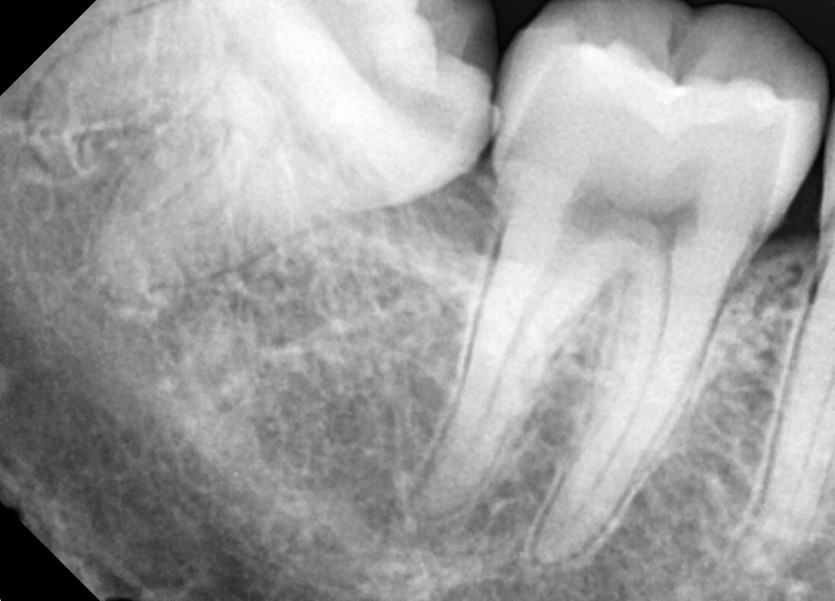

#18,48 사랑니 발치

구강 외과 전문의가 당일 발치했습니다.